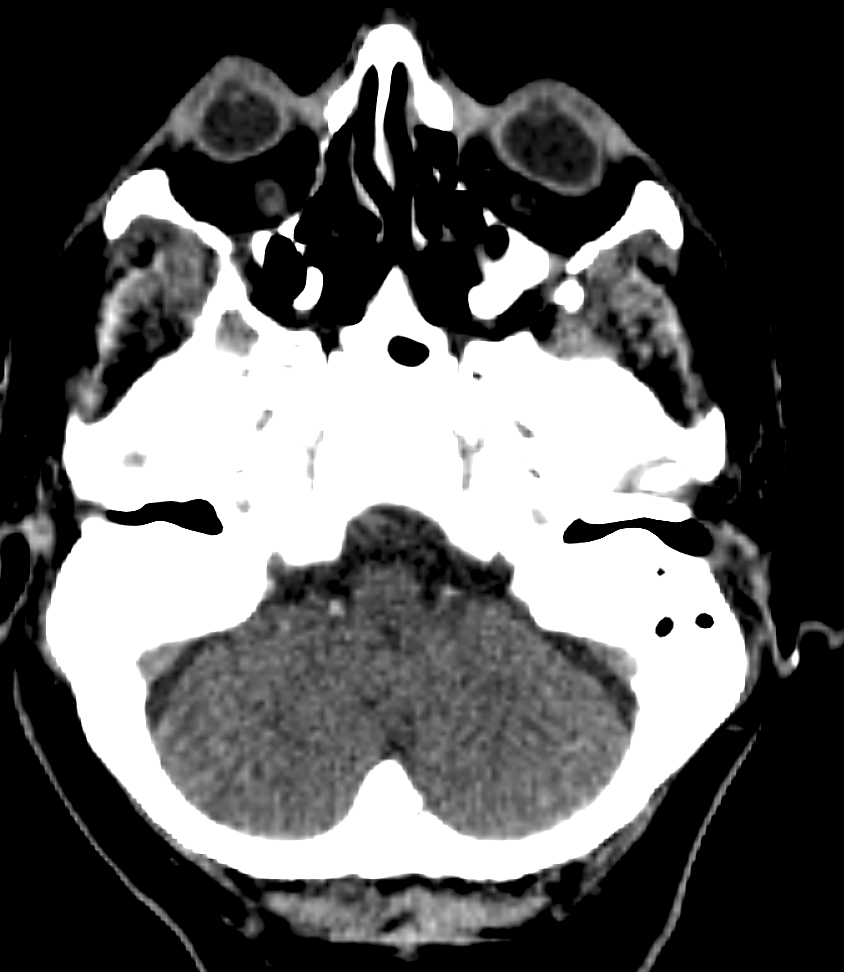

To obtain non-lesion tissue labels, we applied an automatic brain tissue segmentation pipeline based on CTseg222https://github.com/WCHN/CTseg, a deep learning framework for multi-class tissue segmentation in non-contrast CT. In brief, CTseg performs dense pixel-wise classification using a fully convolutional neural network that extracts hierarchical features from CT slices and produces anatomically consistent maps of major tissue compartments [8]. We used CTseg to segment background, cerebrospinal fluid (CSF), skull/bone, and brain parenchyma-related tissues, as show in Figure 2. These outputs served as the baseline tissue segmentation for each slice.

Refer to caption

Figure 2: Example of multi-class tissue segmentation on a representative NCCT slice. CTseg was used to automatically segment normal tissue classes, whereas ischemic infarct regions correspond to manual annotations provided by expert annotators.

All masks were resized to a fixed spatial resolution of 256×256256\times 256 pixels using nearest-neighbor interpolation, preserving discrete boundaries and preventing label mixing. Each mask was converted from a single-channel label map into a one-hot tensor X{0,1}C×H×WX\in\{0,1\}^{C\times H\times W} to enable categorical reconstruction losses during training. Color palettes were used exclusively for the visualization of qualitative results (Figure 2; all training was performed in label space.